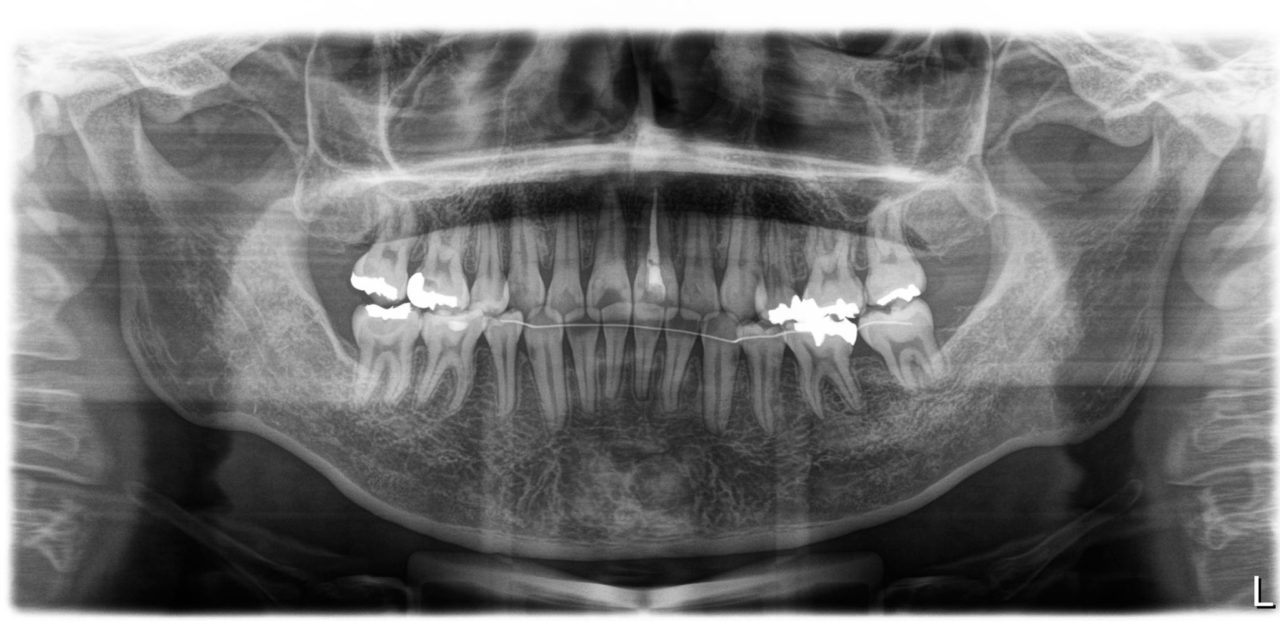

ファイナル パノラマレントゲン

| 備考 | 左上中切歯の根尖性歯周炎で来院されました。根っこの先に過剰歯があり、左上中切歯の神経は死んでいました。根管治療後、歯列不正を改善のために矯正治療を提案しました。小臼歯4本抜歯を伴うものですが、噛み合わせが良くなるだけでなく、口元もかなりすっきりし、審美を得られる可能性があることを説明をしたところ、快く了承をしていただけました。失活歯で予後不良の左下第2大臼歯も抜歯し、親知らずを利用しました。すべての治療期間は23か月かかりましたが、今後の人生が楽しみになる顔貌の良化を遂げたと考えます。ご本人にも非常に喜んでいただけました。 |